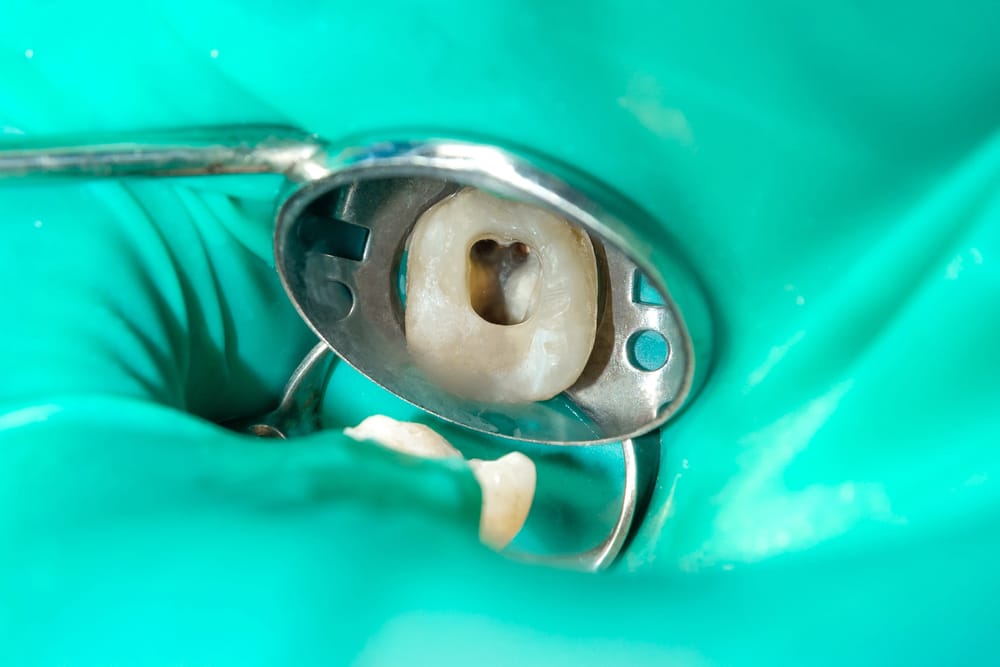

The root canal is the part of your tooth’s root that contains all of the pulp. When this dental pulp becomes infected or inflamed, it must be removed in order to preserve the tooth. The process is relatively simple: we go into the tooth, widen the canal, remove the damaged dental pulp, then fill and seal the canal and tooth.

The treatment is quite straightforward; first, you’ll receive an anesthetic in order to stop any discomfort. Then, the endodontist will create an opening in your tooth in order to access the root. The damaged tissue will be removed, leaving only healthy tissue behind. From there, the dentist will seal off the widened canal, then seal the opening they made in your tooth. In many cases, you may need a crown placed on your tooth. For some serious infections, or difficult to access roots, we may refer you to an endodontist, a specialist who deals with complicated root canal treatments (among other things).